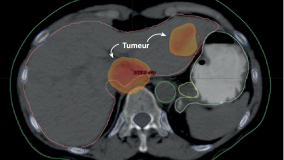

Un nombre record de cellules cancéreuses détruites : la radiothérapie entre dans une nouvelle ère

Les rayonnements ont révolutionné la médecine lorsqu’ils ont été appliqués la première fois au traitement du cancer, en 1901. Cependant, leur utilisation n’a pu évoluer qu’en fonction des innovations techniques.